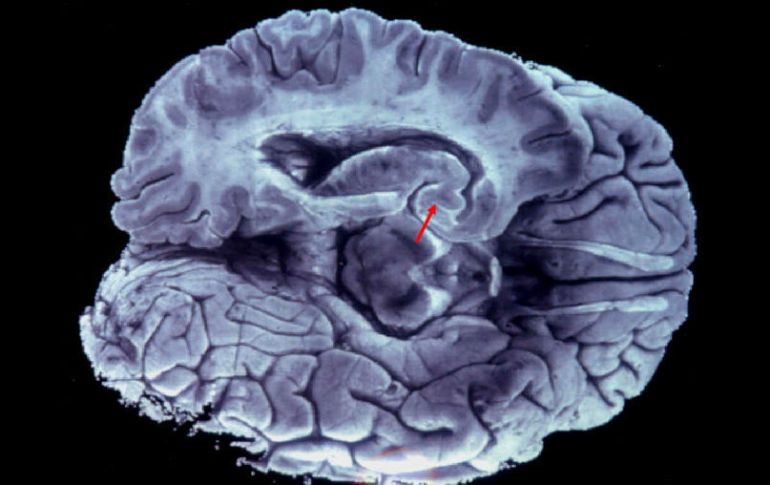

Tecnología | Desarrollan nuevas teorías en banco de cerebros, reinterpretan proteína Tau Científicos mexicanos logran hallazgo acerca del Alzheimer Desarrollan nuevas teorías en banco de cerebros, reinterpretan proteína Tau Por: EFE 29 de diciembre de 2011 - 21:17 hs La teoría formal es que un mecanismo tóxico de la neurona causa que la proteína Tau fosforilada dañe la neurona y cause su muerte. EFE / CIUDAD DE MÉXICO (29/DIC/2011).- Un grupo de científicos mexicanos publicará el año que viene en una revista especializada un hallazgo que podría cambiar la comprensión del Alzheimer, y que han hecho gracias a estudios en el mayor banco de cerebros de Latinoamérica, anunció hoy uno de los responsables del proyecto. En el artículo, que publicará en 2012 la revista europea "Acta Neuropathologica", los científicos plantearán una interpretación nueva del fenómeno de la fosforilación de la proteína Tau en el cuerpo de la neurona, mediante la cual grupos de fosfatos se suman a esa proteína lo que termina por plegar y matar la neurona. Un nutrido número de investigadores de distintas instituciones, encabezados por el científico mexicano Raúl Mena, del Centro de Investigación y de Estudios Avanzados (Cinvestav), participan en el estudio para el que disponen de alrededor de 120 cerebros. El banco de cerebros está ubicado en Ciudad de México, en el departamento de Fisiología, Biofísica y Neurociencias del Cinvestav, y ahí se guardan cerebros seccionados en mitades, una parte de las cuales se mantiene en ultracongeladores a 90 grados bajo cero, y las otras sumergidas en paraformaldehído -una solución química- a cuatro grados. Con los más fríos, los expertos estudian las proteínas del cerebro, y las enzimas que afectan a la proteína Tau, cuyo comportamiento anormal es clave en el desarrollo de la enfermad. El resto se somete a estudios de inmunohistoquímica, en los que se analizan las lesiones características que el Alzheimer produce en el cerebro, como las placas neuríticas y el aumento de marañas neurofibrilares. El banco de cerebros se abrió en 1992 y a fecha de hoy se almacenan allí 18 cerebros mexicanos, unos 50 donados por un centro especializado de Cambridge, 20 de una organización canadiense, 10 de una estadounidense, y unos 20 de Francia que son de personas fallecidas con más de 100 años. Algunos de los órganos fueron recogidos apenas unas horas después de la muerte del paciente, lo que ha permitido a los académicos trabajar con células relativamente frescas. Una parte de los análisis se ha centrado en el estudio temprano del proceso de fosforilación de la proteína Tau en el cuerpo de la neurona, explicó en entrevista con Efe José Luna Muñoz, profesor adjunto de Raúl Mena. La teoría tradicional es que un mecanismo tóxico de la neurona causa que la proteína Tau fosforilada (con los fosfatos añadidos) dañe la neurona y cause su muerte. En el artículo de "Acta Neuropathologica", los investigadores mexicanos plantearán una interpretación diferente de ese fenómeno, que en 2050 afectará a 113 millones de personas, según datos de la Fundación Española de Enfermedades Neurológicas (FEEN). "Estamos sugiriendo que la fosforilación de la proteína Tau es un mecanismo de protección de la neurona para que pueda tener un mayor tiempo de vida", dijo Luna Muñoz. Los científicos mexicanos encontraron que un fragmento (o núcleo mínimo) de la proteína Tau, que se caracteriza por tener una longitud de entre 92 y 95 aminoácidos y que termina en un ácido glutámico específico, "es altamente tóxico". Según Luna Muñoz, la proteína Tau en el Alzheimer se rompe en esa posición del ácido glutámico, lo que desencadena la fosforilación, que conduce a la muerte de las neuronas. "Hay muy pocos grupos de científicos en el mundo que están investigando ese núcleo mínimo, uno Aberdeen (Inglaterra), otro en Alemania, y otro en Chicago", señaló Luna Muñoz. La propuesta del equipo mexicano puede "cambiar la manera en que se trata de detener la formación de la maraña y la fosforilación con fármacos", detalló el investigador. A juicio del experto, es posible que al intentar parar esos procesos "lo que se haga es potenciar más la formación de ese núcleo mínimo". "Lo que se debe buscar es ver qué esta truncando a la proteína Tau. No se trata de combatir la fosforilación ni la maraña sino de que no se produzca la partición en el núcleo mínimo", explicó. Con el empleo de ratones transgénicos, los científicos mexicanos están abocados ya a la tarea de buscar cuál es la enzima que rompe la proteína Tau en ese fragmento de entre 92 y 95 aminoácidos de longitud. Nueve expertos del departamento de Fisiología, Biofísica y Neurociencias, cinco del Instituto de Neurología y Neurocirugía de México, y cinco más del departamento de Biología Celular del mismo Cinvestav participan en el proyecto. Temas Ciencia Alzheimer Lee También Julieta Fierro será homenajeada en la FIL Nobel de Química premia el desarrollo de estructuras metal-orgánicas Nobel de Física para Clarke, Devoret y Martinis por descubrimiento sobre fenómenos cuánticos Nobel de Medicina premia investigación sobre el control del sistema inmunitario Recibe las últimas noticias en tu e-mail Todo lo que necesitas saber para comenzar tu día Registrarse implica aceptar los Términos y Condiciones